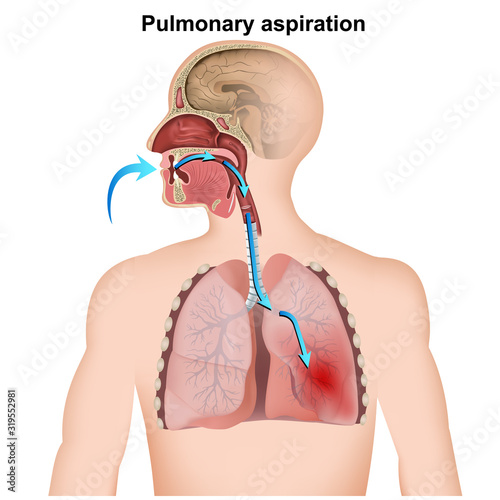

Aspiration - Posters, Wall Art, Canvas Prints